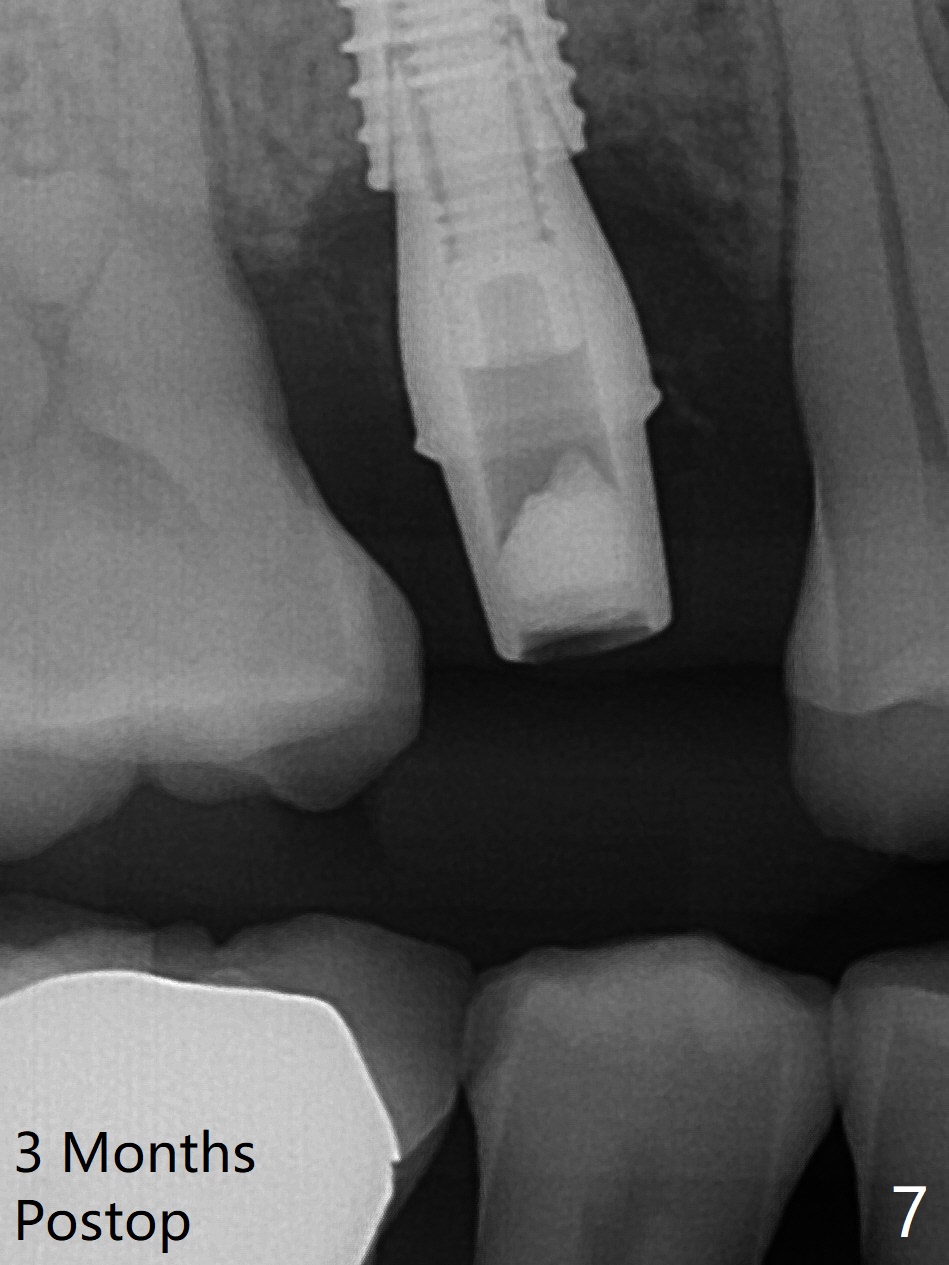

A 61-year-old man cracks the tooth #4 while chewing on a piece of chicken bone (Fig.1,2). Initial osteotomy appears to be able to hold a 16 mm long implant (Fig.3). After sequential osteotomy, a 4x16 mm implant is initially unable to be seated low enough for the buccal crest. Following packing the osteotomy with Vanilla Graft (.5-1 mm) and additional 2-3 mm depth of osteotomy, the implant is placed slightly apical to the buccal crest (Fig.4,5); with placement of Vanilla Graft (*) and a 4.5x4(4) mm abutment, an immediate provisional is fabricated to close the socket. The provisional is removed 3 months postop because of poor local oral hygiene (Fig.6,7). The gingiva is healthy 2-3 weeks later; it is easy to take impression (Fig.8).